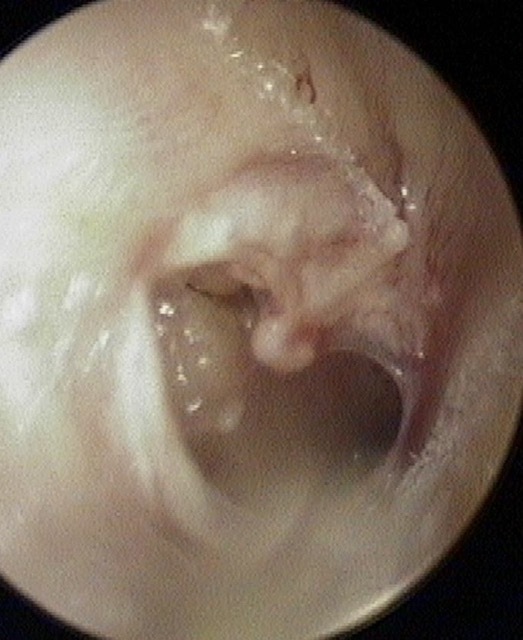

Perforation